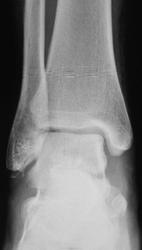

Травма. Пациент направлен на рентгенографию голеностопного сустава

Фрагментарный перелом наружной лодыжки, и ,кажеться, есть отрыв заднего бугорка таранной кости.

Классный перелом-филигранная работа, только верхушечка!

Отрывной перелом нижнего полюса наружной лодыжки. 3 недели в U-лонгете. Затем, даже если не срастается, то уже не болит, можно ходить далее. Перипроцесса не вижу, да и не знаю оного)